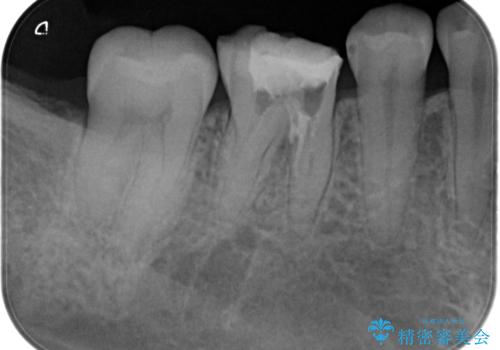

根管内を見てみると、近心根は本来の根管とは違うところを削られて髄床底でパーフォレーションを起こしていました。

また、遠心根でも本来の根管とは逸脱した方向に根管形成されていましたが、修正し充填を行っています。

パーフォレーション部位に関しては、口腔内との交通がなければMTAセメントを用いて修復することで、高い予知性を期待できます。